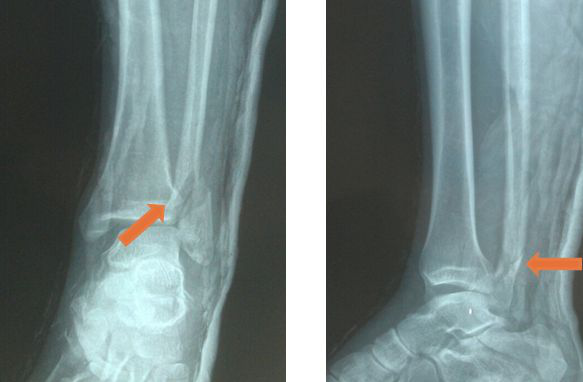

当足外翻程度较小时,垂直暴力被下胫腓联合复合体吸收,其分离程度越大,韧带损伤或撕裂严重程度越大,甚至伴有前后下胫腓韧带附着点撕脱骨折。即Tillaux-Chaput骨折、Volkman骨折、Wagstaffe骨折等。

由于发生Logsplitter损伤时,距骨完全楔入下胫腓联合并轴向移位,此时下胫腓联合完全分离、踝关节完全脱位,可伴有腓骨骨折、内踝骨折或三角韧带断裂,所以从影像学上来看,有时难以直接与Dupuytren骨折相互区别。

典型损伤:距骨完全嵌入下胫腓联合,下胫腓联合复合体完全分离移位,伴或不伴距骨及'天花板'骨折。

非典型损伤:距骨部分嵌入下胫腓中,下胫腓联合分离不完全,踝穴增宽但关节面完整。类似于Dupuytren fracture,也有人把 Dupuytren fracture 称为 Logsplitter 的一种特殊形式。